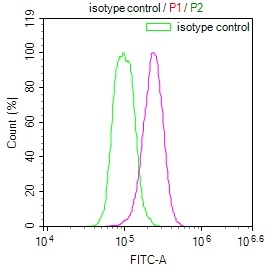

The image on the left is immunohistochemistry of paraffin-embedded Human gastic cancer tissue using CSB-PA196653(ABI1 Antibody) at dilution 1/40, on the right is treated with synthetic peptide. (Original magnification: ×200)